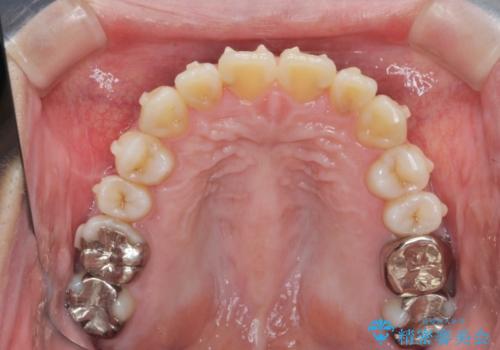

捻れた奥歯 突き出た前歯を治したい

- 出っ歯に見える前歯、捻れてしまった小臼歯の改善を求めて来院されました。

マウスピースでは改善の難しい小臼歯のねじれをまず部分ワイヤー矯正で改善し、その後マウスピース矯正で前歯の突出感を改善します。

時間はかかりましたが、捻れ、かみ合わせ、前歯の角度の改善が達成され満足いただくことができました。